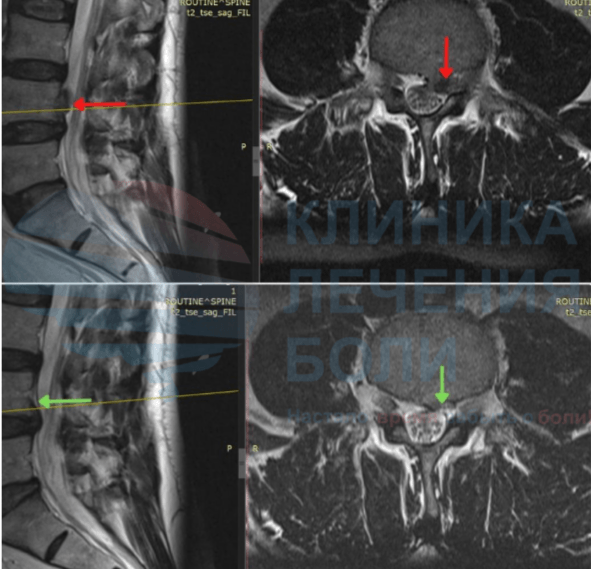

Повышаем вероятность уменьшения или исчезновения грыжи до 94% с помощью метода модулируемой резорбции

Мы первый в Тюменской области центр, который занимается резорбцией грыжи диска (методом безоперационного уменьшение или полного рассасывание грыжи). Благодаря нашему правильному подходу сотни пациентов избежали операций по удалению грыжи диска.